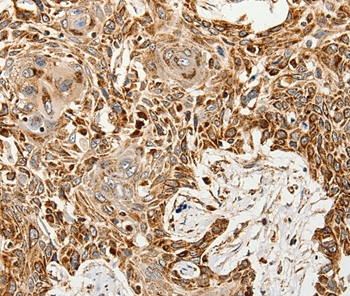

Immunohistochemical analysis of paraffin-embedded Human esophagus cancer tissue using #37247 at dilution 1/60.

应用详情:Immunohistochemistry: 1:50-1:200